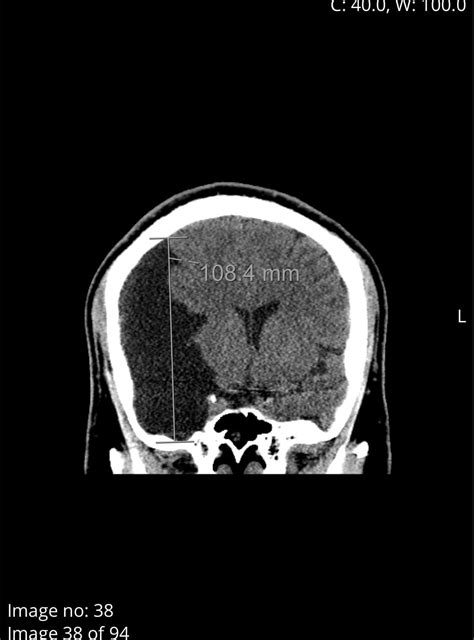

Diagnosing a cyst in brain typically involves a combination of medical history, physical examination, and imaging tests. The most common diagnostic tools include:

• Magnetic Resonance Imaging (MRI)

• Computed Tomography (CT) scan

MRI is often the preferred method for diagnosing brain cysts because it provides detailed images of the brain and can help differentiate between different types of cysts. CT scans are also useful and can be particularly helpful in emergency situations where quick imaging is needed.